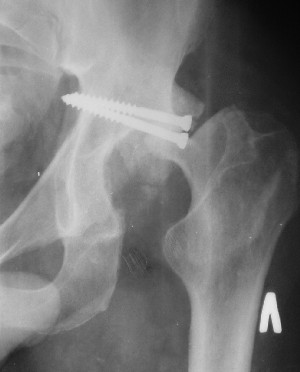

Контрольный снимок перед разрешением нагрузки прямой 13/10/03

Перед разрешением нагрузки боковой 13/10/03

Больной 18 мая 2003 года в автоаварии получил перелом левой вертлужной впадины, вывих бедра. Госпитализирован в один из стационаров области.Вывих вправлен. В последствии бедро вывихивалось еще дважды. На консультацию был представлен снимок от 19.05.03г., больной переведен к нам 3.06.03г. Снимок при поступлении - перелом впадины, задне-верхний вывих бедра. 05.06.2003 г. выполнено открытое вправление вывиха левого бедра и остеосинтез стенки вертлужной впадины двумя винтами. Послеоперационный период без осложнений. Объем движений в левом тазобедренном суставе восстановился полностью. Выписан на амбулаторное лечение в удовлетворительном состоянии с рекомендациями 3 месяца ходить на костылях без нагрузки на оперированную конечность. На контрольных рентгенограммах левого тазобедренного сустава 13.10.2003 г. - признаки консолидации перелома; плотность, форма головки и состояние суставных поверхностей удовлетворительные. Разрешена дозированная осевая нагрузка, на конечность с использованием дополнительной опоры. 19.12.2003 г. больной обратился с жалобами на боли в левом тазобедренном суставе. На рентгенограммах левого тазобедренного сустава 19.12.2003 г., 20.02.04г. - асептичекий некроз головки бедра. 5.04.04г. - эндопротез. Сейчас ходит без трости, не хромает. Особенность эндопротезирования - при удалении винтов прослежена линия перелома заднего края впадины и предложено установить чашку несколько меньшего диаметра, чтобы она была покрыта несломанной частью.